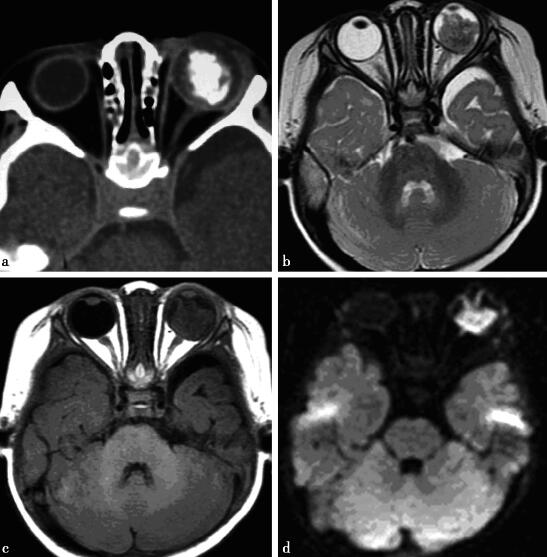

病例2-3-1,女性,2岁,2个月大时被发现左瞳孔发白。体格检查:左眼底窥不清。

病例2-3-1:MRI T1WI、T2WI压脂及T1WI压脂增强。

图1a,CT平扫示左眼球增大,球内肿块占据大部分玻璃体,中央可见大块钙化。图1b,轴位T2WI示不均等高信号。图c,轴位T1WI呈等信号,视神经球内段未见增粗,视交叉和视束未见异常。图1d,DWI呈明显高信号、T2-FLAIR序列肿块呈稍低信号,残留玻璃体呈稍高信号

病例2-3-1,视网膜母细胞瘤。